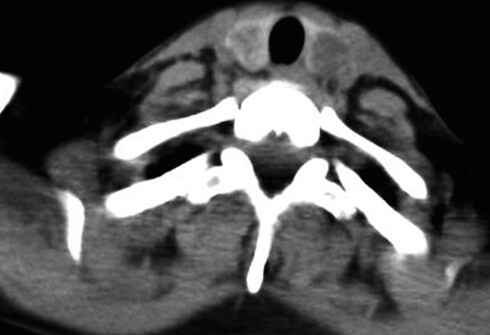

갑상선암 수술 방법은 수술을 하는 위치에 따라서 대표적으로 3가지 정도가 있습니다. 아주 간단하게 설명을 드리면 목을 바로 절제해서 수술하는 방법, 구강을 통해서 수술하는 방법, 겨드랑이를 통해서 수술하는 방법이 있습니다.

갑상선암에 걸리신 분들은 대부분 목을 통해서 바로 갑상선을 절제하는 수술을 많이 진행하십니다. 수술 방법이 쉽고, 빨리 끝나기 때문에 갑상선암 수술 중에서 가장 많이 진행하는 수술 방법입니다.

1. 목으로 하는 수술?

하지만 목으로 할 경우 목에 흉터가 남기 때문에 여성분들 같은 경우 난이도가 좀 더 높지만 흉터가 거의 보이지 않는 구강이나 겨드랑이를 통한 수술을 선호하기도 합니다. 하지만 최근에는 의료 기술이 좋아져서 목에 흉터가 남더라도 티가 잘 나지는 않습니다.

수술 난이도에 따라서 겨드랑이와 구강으로 통한 수술은 당연히 수술비가 많이 나오며, 목을 통해서 바로 갑상선암을 제거하는 수술이 비용이 가장 낮게 나옵니다. 목으로 수술할 경우 가장 가깝고 정확하게 갑상선암을 제거하기 때문에 흉터 외에는 다른 수술 방법에 비하여 장점이 많다고 보셔도 됩니다.